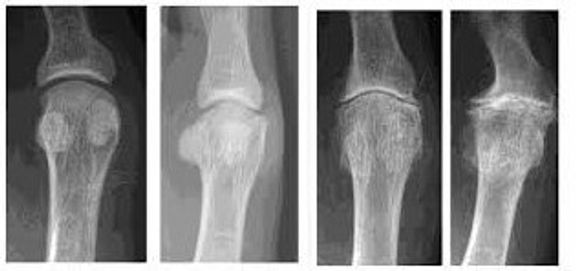

Pictured are comparison x‑rays of Hallux Limitus stages 1 – 4, from left to right. Notice the narrowing of the joint and the destruction of the underlying sesamoid bones, which serve as a fulcrum for propulsion.

Stage 3 –The joint has little remaining motion, and there is significant structural loss marked by bony build-up around it. Grinding with any attempted joint motion is common, along with an increase in pain, swelling, and compensatory alterations in gait. Surgical intervention is necessary at this point. Orthotics, physical therapy, and rehabilitation will likely be done after surgery.

Stage 4 (hallux rigidus)–Auto-fusion of the joint has occurred. The joint may not be painful at this point, but the function is completely lost. At this point, an accommodative orthotic may be of benefit, or surgical intervention may be necessary.